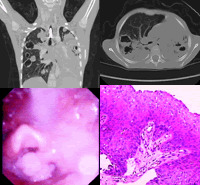

(四)喉結核

原發者少多繼發於開放性肺結核早期患者感喉內乾燥不適或微痛用聲易疲勞或輕度聲嘶檢查可見喉黏膜蒼白也有一側聲帶充血者晚期聲嘶顯著檢查喉黏膜有潰瘍常位於一側聲帶或杓間區潰瘍表淺邊緣不整齊有偽膜復蓋X線胸部透視胸大片活組織檢查可確診。